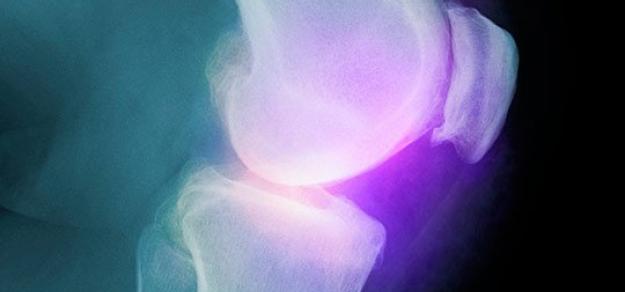

Celecoxib para artrosis. Grandes reservas en cuanto a la evidencia disponible

Cochrane Rev, 22 de mayo de 2017 Los autores tienen grandes reservas sobre los resultados debido a la participación de la industria farmacéutica y datos limitados. No se pudieron obtener los datos de tres estudios, que incluyeron 15.539 participantes, y se clasificaron como aguardando evaluación. La evidencia actual indica que el celecoxib es ligeramente mejor que el placebo y algunos AINEs para reducir el dolor y mejorar la función física, Esta mejora puede no ser clínicamente significativa